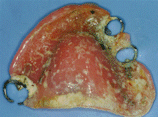

寝たきりの方の入れ歯と口腔内 |

しろっぽいところはバイキンの塊。 口腔の機能が悪いと自浄作用も落ちて汚れが繁殖しやすい |

話す、食べることがないと口腔内の環境はとたんに悪くなる。 |

嚥下の機能低下があるとこれらのバイキンが気管を通して肺に入ってしまう。 |